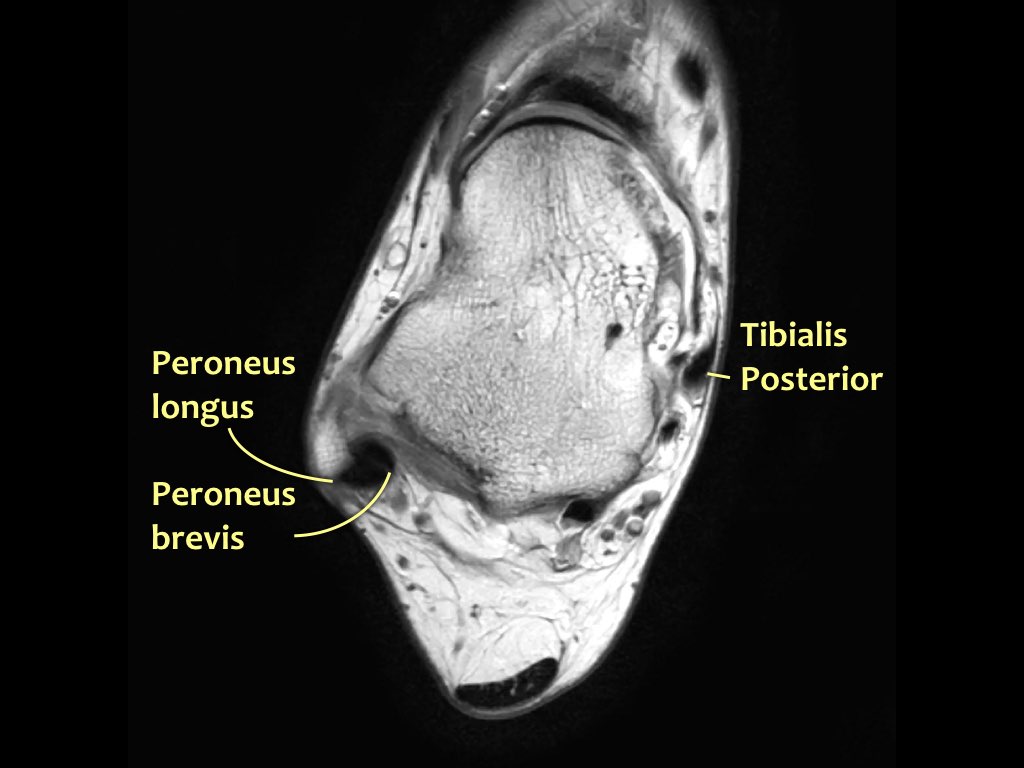

Giải phẫu trên mặt phẳng cắt ngang

Các gân có thể được chia thành bốn khoang:

- Khoang ngoài

- Gân cơ mác dài (Peroneus Longus)

- Gân cơ mác ngắn (Peroneus Brevis)

Gân cơ chày sau

Gân cơ chày sau là gân bị tổn thương thường gặp nhất.

Bệnh lý gân biểu hiện bằng tình trạng sưng to bất thường của gân, tuy nhiên cần lưu ý rằng gân chày sau bình thường có thể có kích thước gấp đôi gân cơ gấp các ngón chân dài.